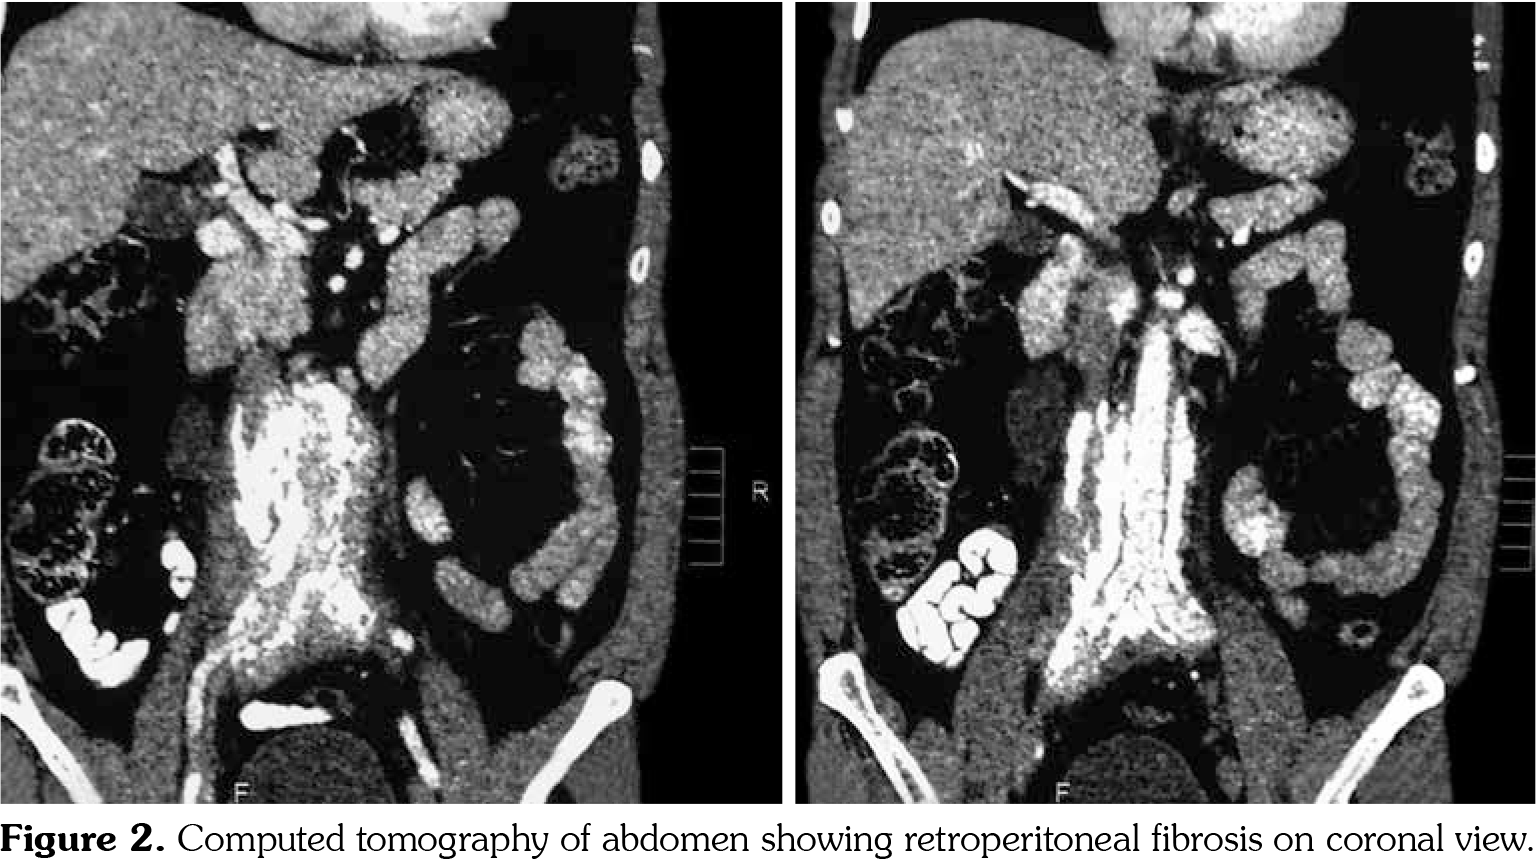

On investigations, his complete blood count was normal. Erythrocyte sedimentation rate was 88 mm in first hour. Random blood sugar was 93 mg/dL. His serum urea was 26 mg/dL and serum creatinine was 1.1 mg/dL. Liver function tests were within normal limits. Chest X-ray revealed non-homogenous opacities in bilateral lung fields. Pulmonary function tests revealed forced expiratory volume in one second (FEV1) of 61% and forced vital capacity (FVC) of 73%. FEV1/FVC ratio was 84%. Two-dimensional echocardiography was within normal limits. Ultrasonography of the abdomen revealed small-sized right kidney (6.9x2.9 cm) with dilated pelvi-calyceal system and dilated proximal ureter. Computed tomography (CT) of the abdomen revealed medial deviation of right ureter and presence of retroperitoneal soft tissue along infra-renal aorta and peri-caval area with calcification extending up to iliac vessels suggestive of RPF (Figures 1, 2, 3, and 4). High-resolution CT of the chest confirmed presence of interstitial lung disease (ILD). ANA profile (ENA) revealed that anti-U1 snRNP was strongly positive. Rest of the autoantibodies were negative. His serum immunoglobulin G levels were within normal limits. Thus, we arrived at a diagnosis of MCTD with RPF and ILD. He was started on mycophenolate 720 mg twice daily, hydroxychloroquine 200 mg once daily and deflazacort 6 mg once daily for MCTD, pirfenidone 400 mg twice daily for ILD and tamoxifen 20 mg once daily for RPF. On follow-up at six months, he was doing physically well. His symptoms of cough were reduced and dyspnea improved from NYHA class IV to class II. Repeat pulmonary function tests revealed FEV1 of 59%, FVC of 71% and FEV1/FVC ratio of 84%. However, repeat ultrasonography of the abdomen did not reveal any significant change in pelvi- calyceal system.